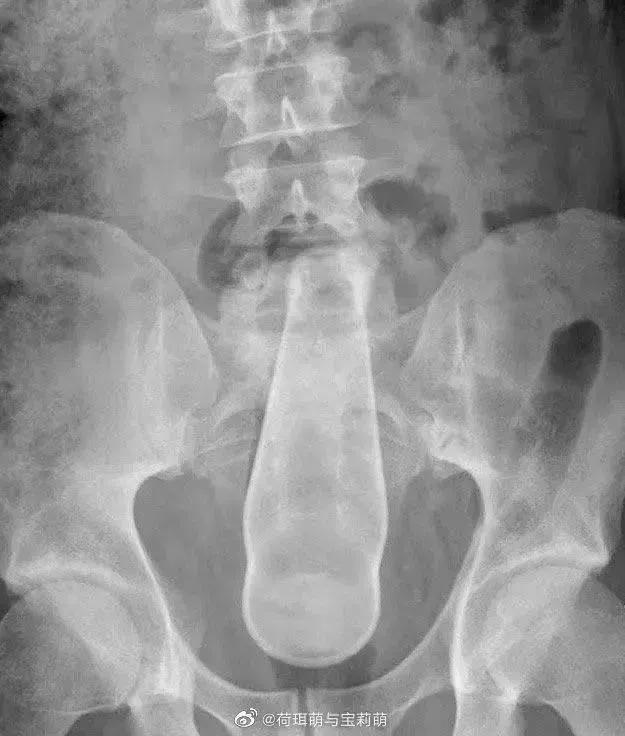

前段时间刷微博看到肛肠科医生发的X光照,一名男性的直肠里被塞入了一只足球。

是的,你没看错,就是国足怎么踢都进不了的那种,充好气圆滚滚的,如假包换。

塞进去的东西就比较五花八门了,沐浴露、胡萝卜、鸵鸟蛋、水果刀、啤酒瓶,甚至还有活物……